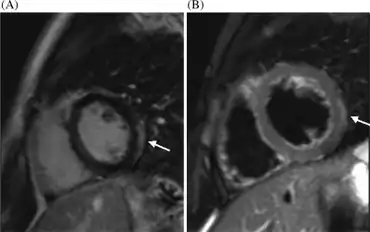

Cardiac magnetic resonance imaging (cMRI or CMR) has been shown to be very useful in diagnosing myocarditis by visualizing markers for inflammation of the myocardium.[28] Recently, consensus criteria for the diagnosis of myocarditis by CMR have been published.[29]